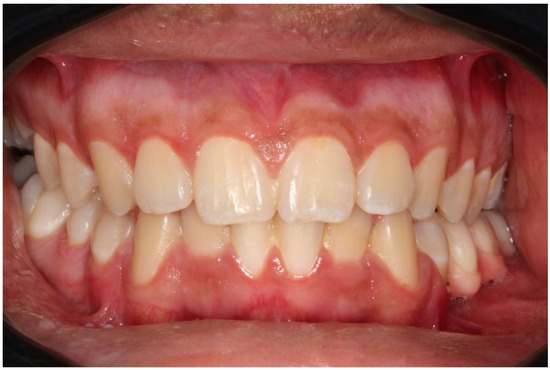

2.1. Case 1

2.2. Case 2